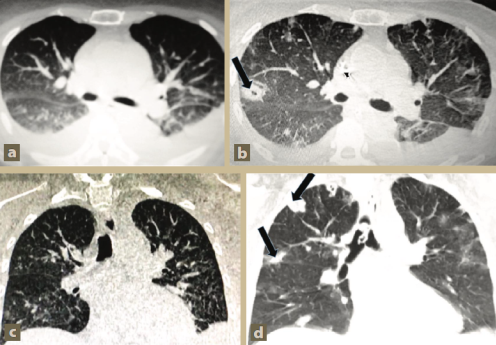

Una tomografía axial computarizada de tórax realizada el día del ingreso mostró derrame pleural bilateral e imágenes sugestivas de “vidrio despulido” en la base pulmonar derecha (figura 2a). Un ultrasonido abdominal evidenció riñones aumentados de tamaño (12 y 13 cm, respectivamente), con disminución general de la densidad y pérdida de la relación corteza-médula.

Figura 2 Tomografía axial computarizada de tórax al ingreso y después de 15 días de hospitalización

Una nueva TAC de tórax, realizada 15 días después de la inicial, mostró la aparición rápida de lesiones nodulares difusas bilaterales, algunas de ellas cavitadas (figura 2b).